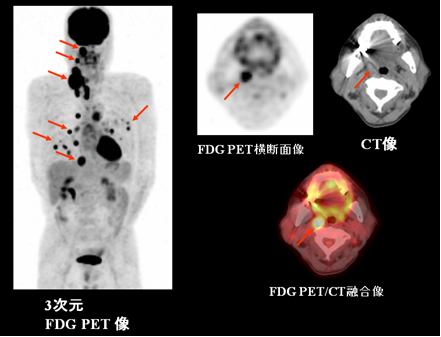

Ct検査よりがん組織と正常組織の区別が明確でct検査とは異なる情報からがんの深さや広がりリンパ節への転移の有無を調べます 7超音波エコー検査 首の表面から超音波をあ てそのはね返りをモニターで見ながら確認. 下咽頭癌の進展範囲を読影する際のチェックポイント 腫瘍の最大径 喉頭への進展の有無 軟骨浸潤の有無 上下方向への進展範囲の決定中咽頭頸部食道 軟部組織浸潤の有無特に梨状癌 梨状窩尖部への進展の有無.

頭頸部癌 最近の診断 治療の進歩 耳鼻咽喉 頭頸科 順天堂医院